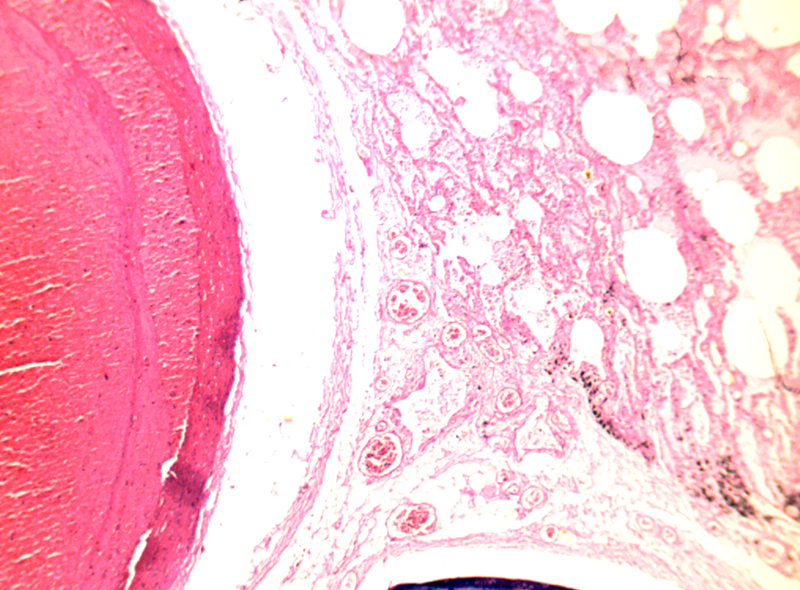

靜脈血栓